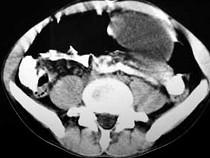

问题 男,33岁,腹部外伤后两月余,腹部疼痛,行CT扫描所见如图,最可能的诊断是 ( )

选项 A.急性胰腺炎 B.慢性胰腺炎 C.胰腺创伤性假性囊肿 D.畸胎瘤 E.腹腔包裹性积血

答案 C